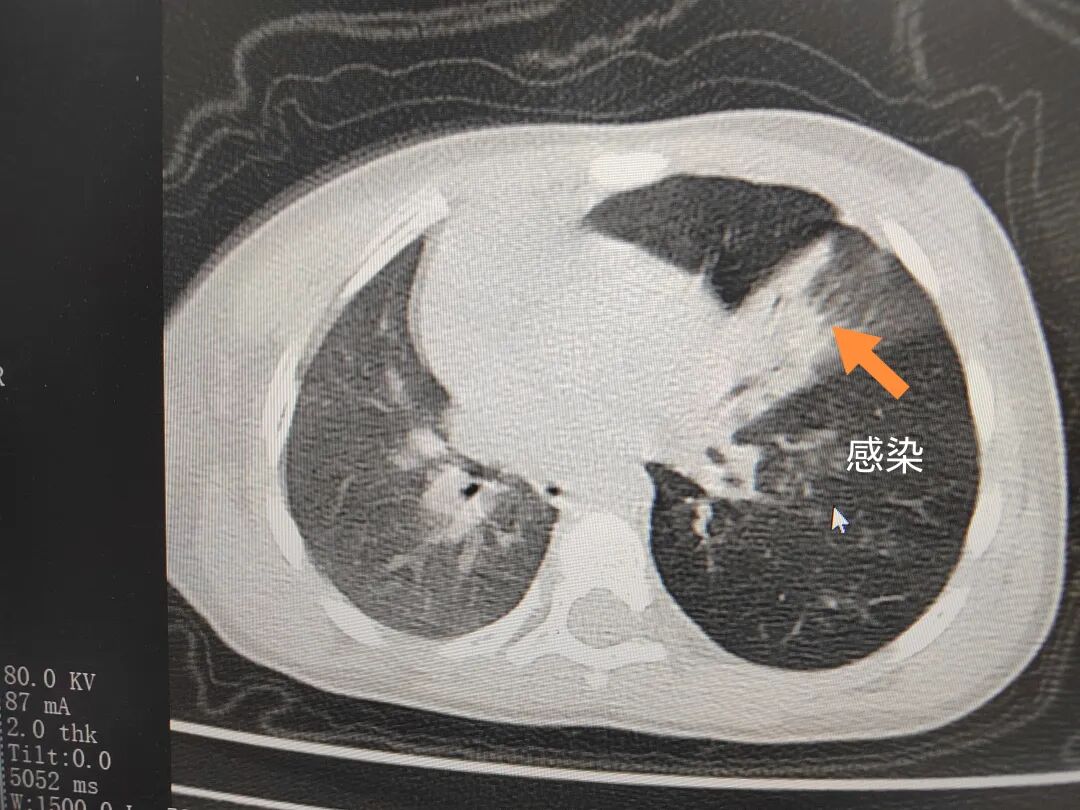

三天后(11月13日),趙寶出現(xiàn)高熱、咳喘加重,家長著急了,再次帶他來到醫(yī)院。CT檢查顯示左肺過度充氣,左肺上下葉支氣管主干見不規(guī)則高密度影,左肺上葉可見大片狀密度增高影,縱隔窗實變,提示為“左側(cè)支氣管內(nèi)異物并繼發(fā)性改變,左肺上葉舌段肺膨脹不全”。

市二院小兒呼吸內(nèi)科副主任楊亞娟介紹,異物誤入氣道可能導(dǎo)致氣道阻塞,嚴重時可引發(fā)窒息,甚至危及生命。若異物進入支氣管,造成不完全堵塞,可引起阻塞性肺氣腫;如完全堵塞支氣管,則可能導(dǎo)致肺組織萎縮,形成肺不張。此外,若異物存留時間較長,或為植物性異物,容易合并細菌感染,產(chǎn)生膿性分泌物,進而發(fā)展為肺炎。她強調(diào),盡早診斷并取出異物,是減少并發(fā)癥、降低病死率的關(guān)鍵。